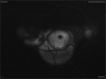

Figures